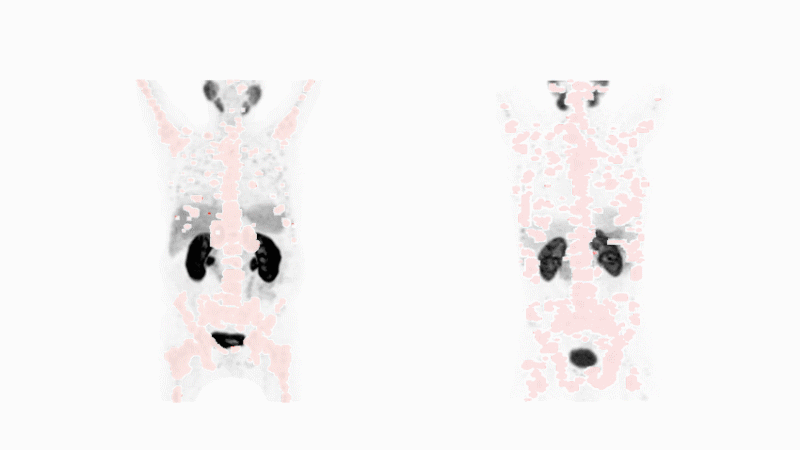

Nuclear medicine has a diagnostic component. It uses the same tumor-specific molecule as the therapeutic, but delivers radioactive atoms that have the potential to unveil cancer. Those atoms emit gamma rays that are detected by specialized imaging devices. If the medicine finds the specific form of cancer, the approach will reveal the cancer no matter where it is throughout the body - even in tiny spots no surgeon could see or excise. Image by Michael Hofman courtesy Journal of Nuclear Medicine. Animation by Fidelis Onwubueke

Nuclear medicine also has a diagnostic component. The diagnostic uses the same tumor-specific molecule as the therapeutic, but delivers radioactive atoms that have the potential to unveil cancer.

These atoms emit a form of energy that can be detected outside of the body by imaging scanners. This form of radiation enables doctors to see the cancer no matter where it has spread in the body.

The diagnostic will only reveal a patient’s cancer if the molecular puzzle pieces match. If they do, targeted radioligand therapy using that same tumor-specific molecule is potentially a good match for the patient.